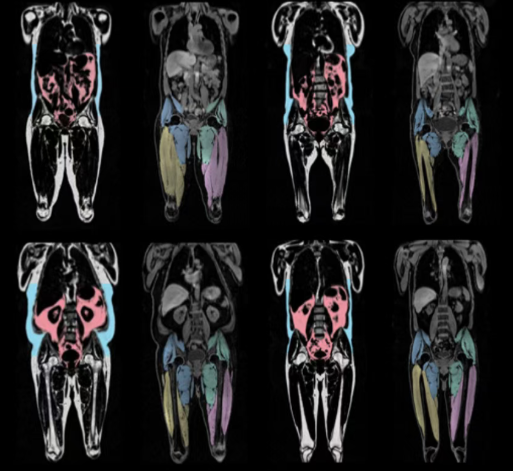

2025年8月,《歐洲心臟雜志》(EHJ?)上發(fā)表的一項(xiàng)研究發(fā)現(xiàn):內(nèi)臟脂肪累積與男女心血管衰老的加速相關(guān),想要心血管衰老慢一點(diǎn):兩個(gè)地方要“粗”——大腿粗、臀圍粗、一個(gè)部位要“細(xì)”——腰要細(xì)。

2.1萬名參與者被納入研究,通過全身成像來得出身體脂肪體積和分布,分析與心血管衰老之間的關(guān)系。該研究發(fā)現(xiàn):腹部的脂肪累積,會(huì)加速男性的心血管衰老;腿部和臀部的脂肪累積,會(huì)減緩女性的心血管衰老。

研究截圖

具體來說:女性的腿部和臀部脂肪每增加1公斤,減緩心血管衰老約0.5年,內(nèi)臟脂肪每增加1升,加速心血管衰老約0.66年。